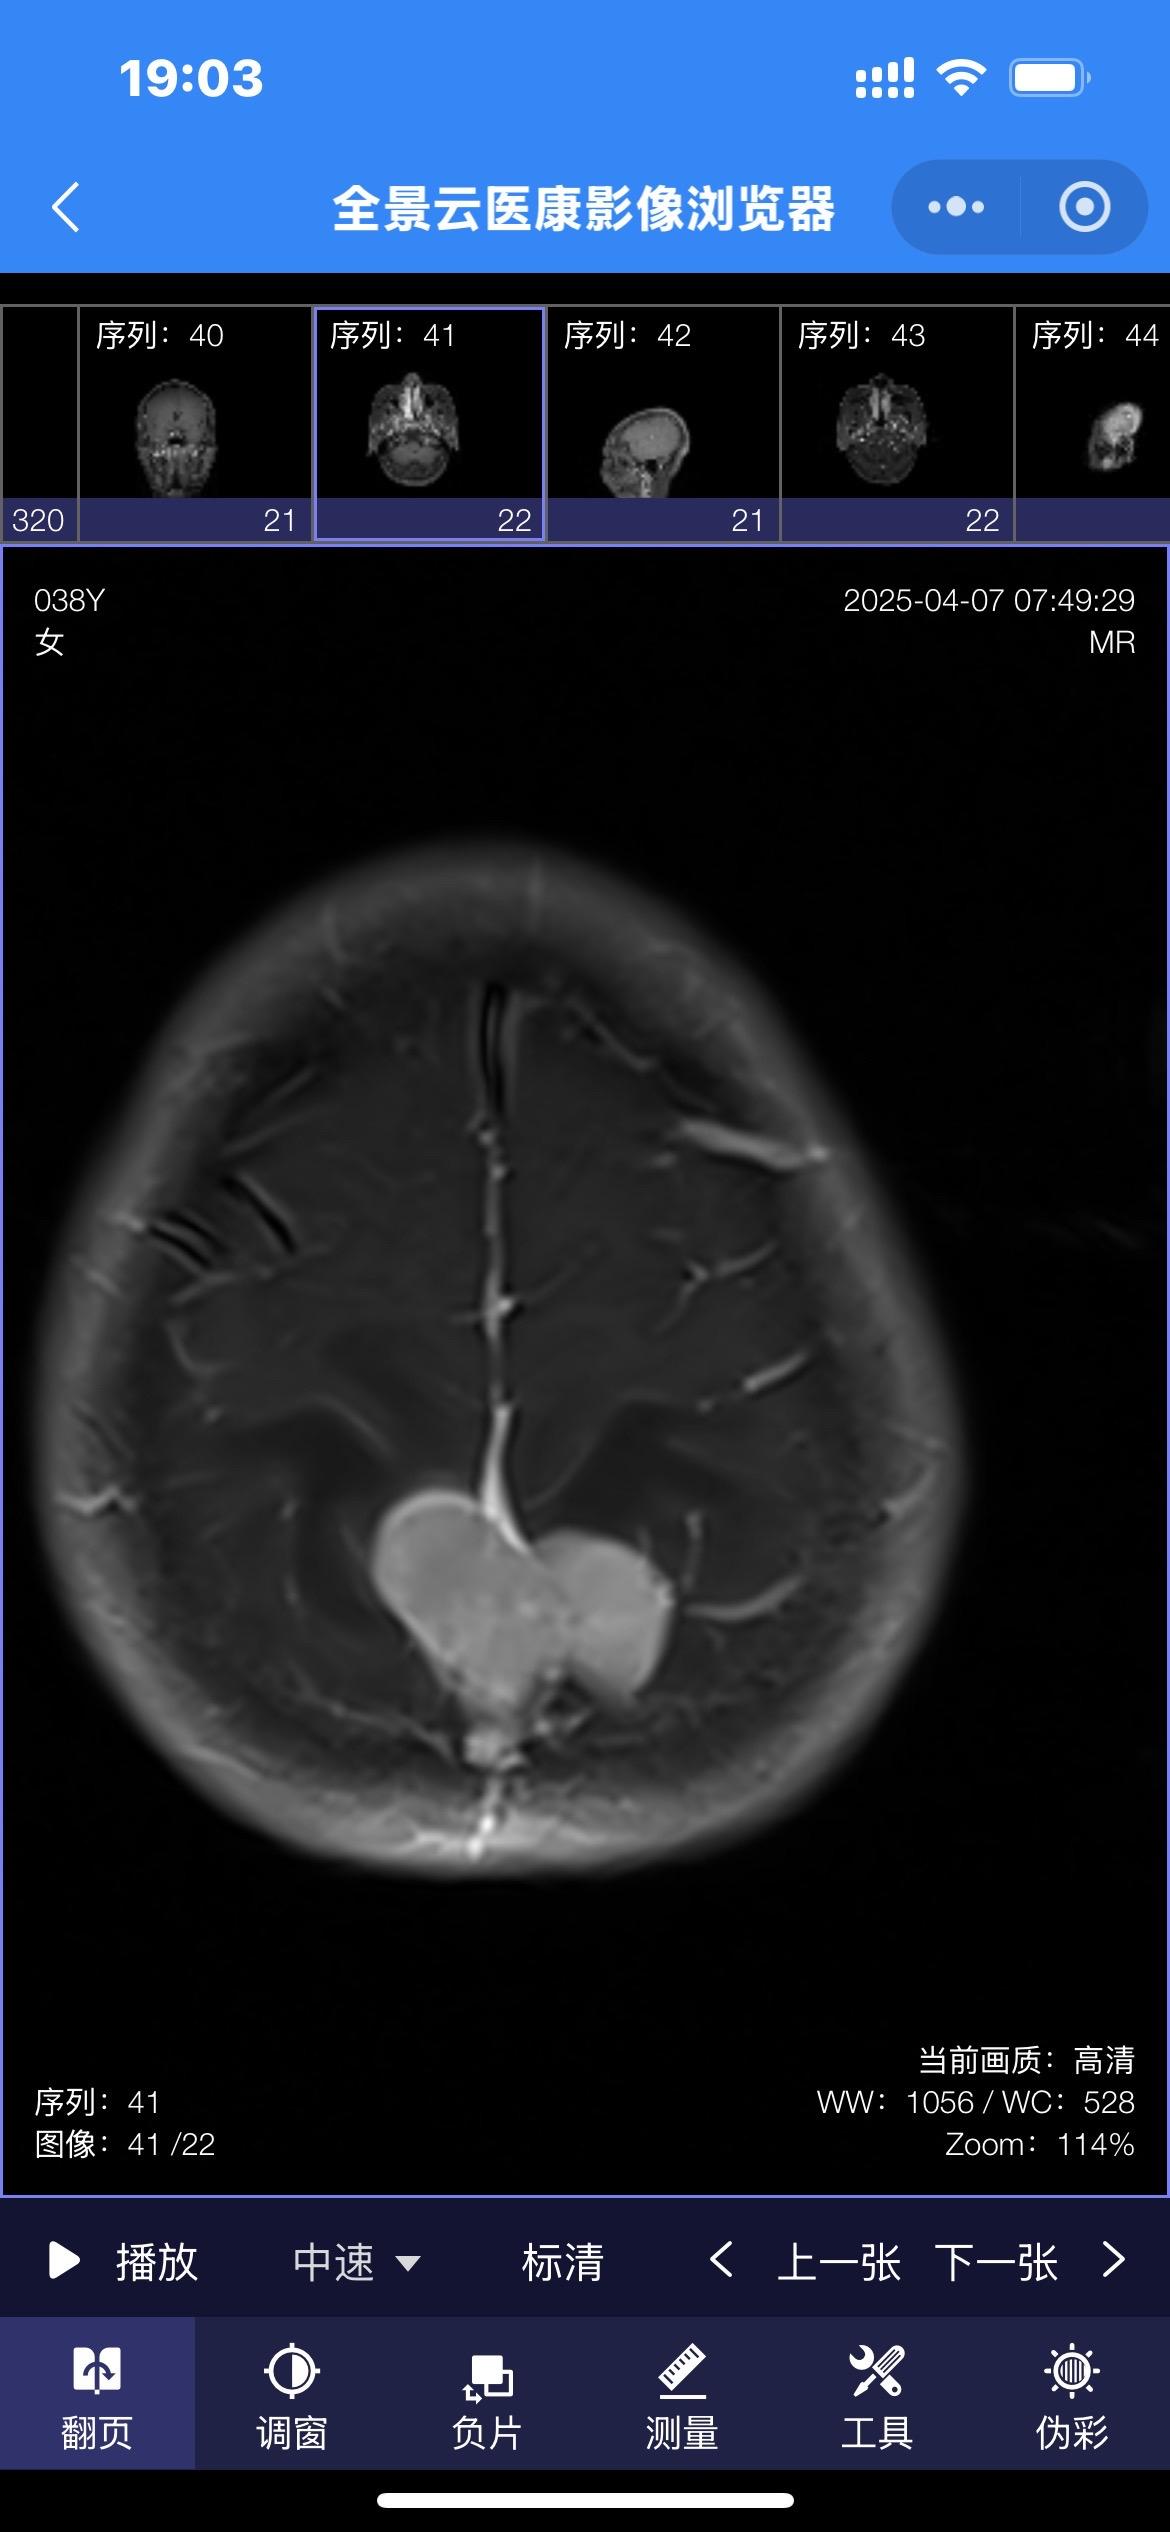

第一眼就诊断为颅咽管瘤,病理报告却不是。55岁女性因记忆力下降,有时思...

2025-04-07 09:07